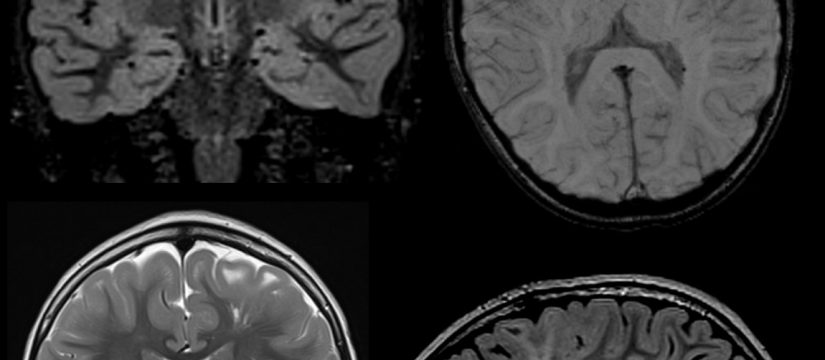

Historia Clínica

Niño de 4 años en estudio por crisis comiciales.